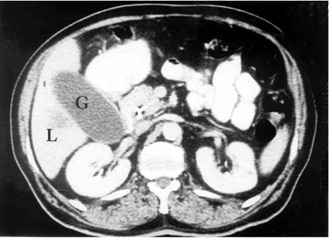

1. טומוגרפיה ממוחשבת - בדיקת הבחירה לאבחון שאתות בלבלב. בעזרתה מודגמות כיום השאת ומידת התפשטותה באחורי הצפק (רטרופריטונאום), כולל חדירה לכלי הדם הגדולים. דיוק האבחנה בטומוגרפיה ממוחשבת הוא גבוה, בלא קשר למיקום השאת (תצלום 19.9).

לעתים ייראו כיס מרה גדול על-שם קורבזיה (תצלום 20.9) והרחבה של דרכי המרה החוץ והתוך-כבדיות (תצלום 21.9).

בטומוגרפיה ממוחשבת ספירלית אפשר לראות את כלי הדם ולהבדיל בין שאת מרובת כלי דם לשאת דלת כלי דם, וכן לזהות את מיקומה וגודלה. בעזרת טומוגרפיה ממוחשבת אפשר לאתר את השאת בלבלב, ולהחדיר אליה מחט כדי לדגום אותה – FNA (תצלום 22.9).